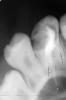

Денис481 Опубликовано 18 апреля, 2013 Поделиться Опубликовано 18 апреля, 2013 новую тему чтоб не создавать напишу тут,пришла девушка,скололась пломба,снимок,под корону зуб,начали перелечивать,распломбировал,начал с ковровых,затем м2,до 30 небный 0,4 до 20 щечные 0,4,по апексу все в норме,замерял,разработал,контрольный снимок все в норме,затем закрыл,думаю еще снимочек и тут такая бяка,не пойму что там,штифт по замерам вставлял,может силлер вышел,конусными делал Ссылка на комментарий

Денис481 Опубликовано 18 апреля, 2013 Поделиться Опубликовано 18 апреля, 2013 Еще супер кофер одел,перепутал))) Ссылка на комментарий